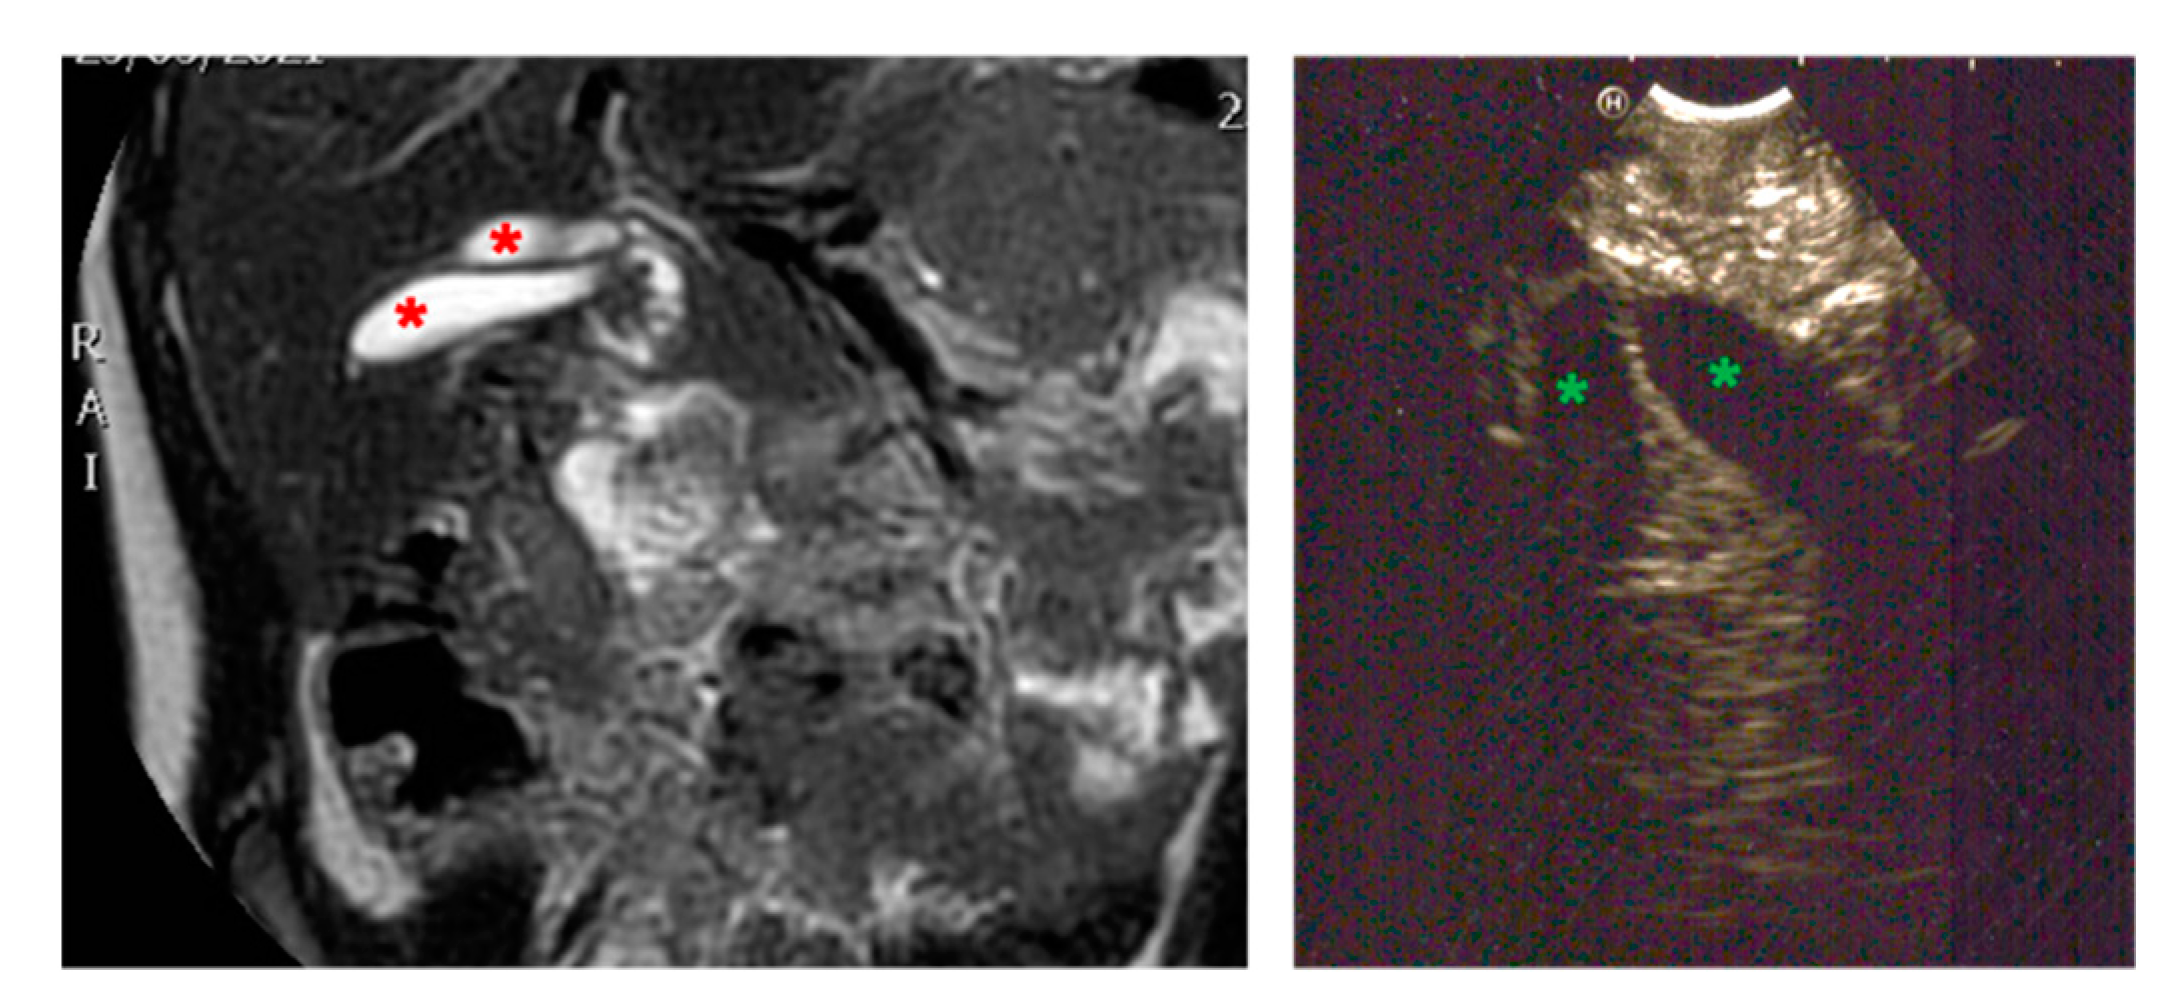

3.2.1. Congenital Malformations (Duplication Cysts)

| Radiological investigations | MR, US, EUS, X-ray | US, MR, CT-scan, barium swallow | US, MRI | |

| Endoscopic instrumentation | EBUS | EBUS | EG-3870UTK Linear-Array Ultrasound Gastroscope | |

| Management | MIS (laparoscopic resection of gastric duplication cysts) | MIS (thoracoscopic resection of esophageal duplication cyst) | Planned endoscopic removal by unroofing and mucosectomy | |

| Endoscopic Advantages/Limitations | Reduction in the diagnostic possibilities by identification of cysts surrounded by gastrointestinal wall layers | Definition of the relationships with surrounding tissues | Anatomical definition of surrounding structures (in particular, the biliary tree and pancreatic duct) | |

| Symptoms | Acute pancreatitis, pain in right hypochondrium | Icterus, pancreatitis | Chronic pancreatitis with choletithiasis, genetic-based | No |

| Diagnosis (prenatal evaluation yes/no) | Cholelithiasis and choledocholithiasis in duodenal atresia (duodeno-jejuno anastomosis at birth) and pancreas divisum (yes) | Choledochal cyst (Todani I) and choledocholitiasis (no) | Mutation of the gene PRSS1, Cholelitiasis, pancreatic duct duplication (no) | Gallbladder duplication Annular pancreas Duodenal duplication (yes) |

| Radiological investigations | US, MR, CT Scan, VR HMD | US, Cholangio MR | US, X-ray, Cholangio MR, CT, VR HMD | US, Cholangio MR, CT |

| Endoscopic instrumentation | EG-3870UTK Linear-Array Ultrasound Gastroscope | EBUS + Duodenoscope | Duodenoscope, EG-3870UTK Linear-Array Ultrasound Gastroscope | EBUS |

| Management | MIS (laparoscopic cholecisectomy) with LCBDE | 1. ERCP + sphincterotomy + stone removal 2. Open surgery: choledochal cyst removal and Roux-en-Y bilio-digestive anastomosis | 1. EUS + ERCP + stent placement + sphincterotomy + DASE; MIS (laparoscopic cholecystectomy) with LCBDE 2. ERCP and pancreatic stent replacement | MIS (laparoscopic cholecystectomies) with attempted LCBDE (failure for fibrosis) |

| Endoscopic Advantages/Limitations | Anatomical definition ERCP technically impossible for difficulties in reaching the papilla | Diagnostic and therapeutic procedures | Effective biliopancreatic drainage permitted postponed cholecystectomy and pancreatic preservation | Anatomical definition |